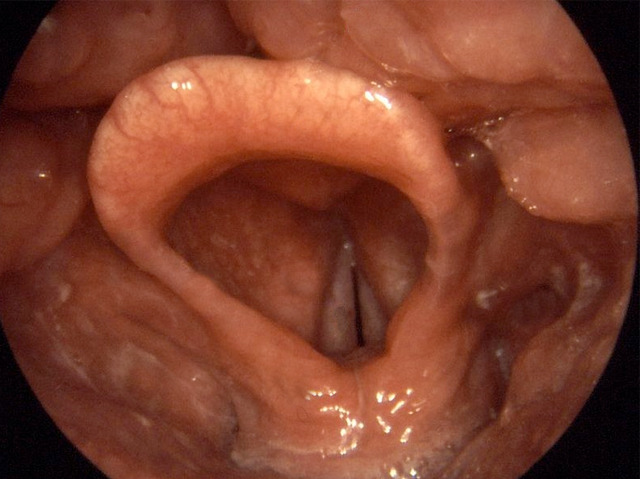

British Prime Minister, Disraeli observed: “There is no greater index of character so sure as the voice”. Now new research suggests that how we speak could divulge even more about us than how sincere or confident we are. Parkinson’s disease gradually degenerates cells of the central nervous system affecting a wide range of body functions. Yet it can be difficult to diagnose. A voice disorder may be one of the earliest signs as the disease strikes the vocal cords (healthy ones pictured; paired whitish strips centre). Effects on speech include reduced loudness, increased vocal tremor, and breathiness. By applying computer algorithms to analyse voice recordings, researchers have identified sound patterns that look promising for distinguishing patients with early Parkinson’s. To increase the power of their analysis, the team wants to hear more voices with and without the disease. By phoning-in anonymously to say “aaaah”, everyone can participate in biomedical research.